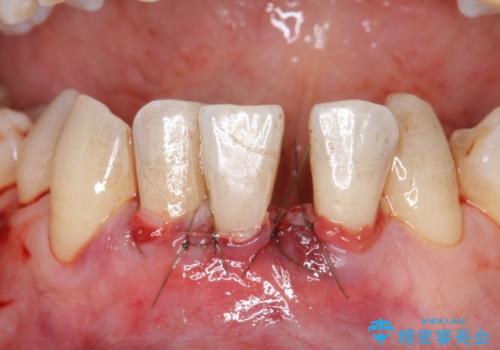

- 矯正前に下顎前歯の歯肉退縮の改善と予防のために歯肉移植を行った症例です。

上顎口蓋部から結合組織を採取し、下顎前歯部に移植しました。